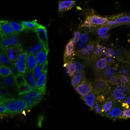

Onderzoekers ontdekken nieuwe route naar zelfdoding kankercellen

Chemotherapie doodt kankercellen. Maar hoe deze cellen sterven, blijkt anders dan tot nu toe werd gedacht. Onderzoekers van…